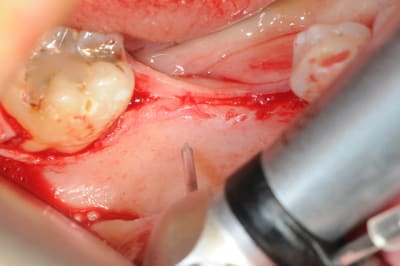

4 après ouverture

1: foret de perçage pour que l'os puisse apporter du sang.

(initialement, c'est un foret pour les pins densply)

2-3: je fais des petits trous (comme Serge)